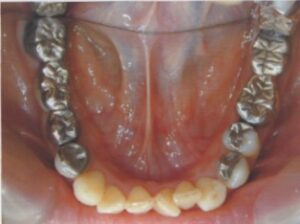

- 10年前から他の歯科医院にて部分的な治療を受けたが、見た目が良くない・噛めないとのことで再治療を希望された。アングルクラスⅠであった。左上奥歯がない。

- 上顎左側にインプラントを3本し、

- オールセラミック4本にて被せ物を行なった。

- 審美的な仕上がりで、患者自身も満足した。23年経過し良好である。

現在は2〜3ヶ月おきのメインテナンス中である。